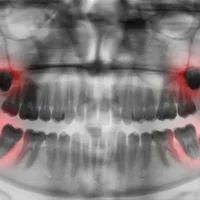

Dents de sagesse

Bouche et dents